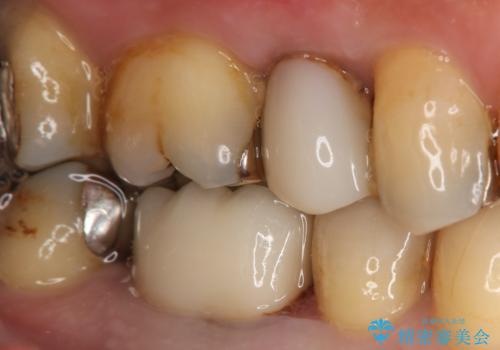

奥歯が痛む オールセラミッククラウン

- 咬んだ時に右下奥歯に痛みがあるとの事で来院された患者様です。

歯の神経は壊死していたため、精密根管治療と補綴治療を計画しました。

セラミックでの治療を希望されたので補綴はオールセラミッククラウンでの治療を選択しました。

痛みは完全に取り除かれ、咬合時の違和感もなく経過は良好です。